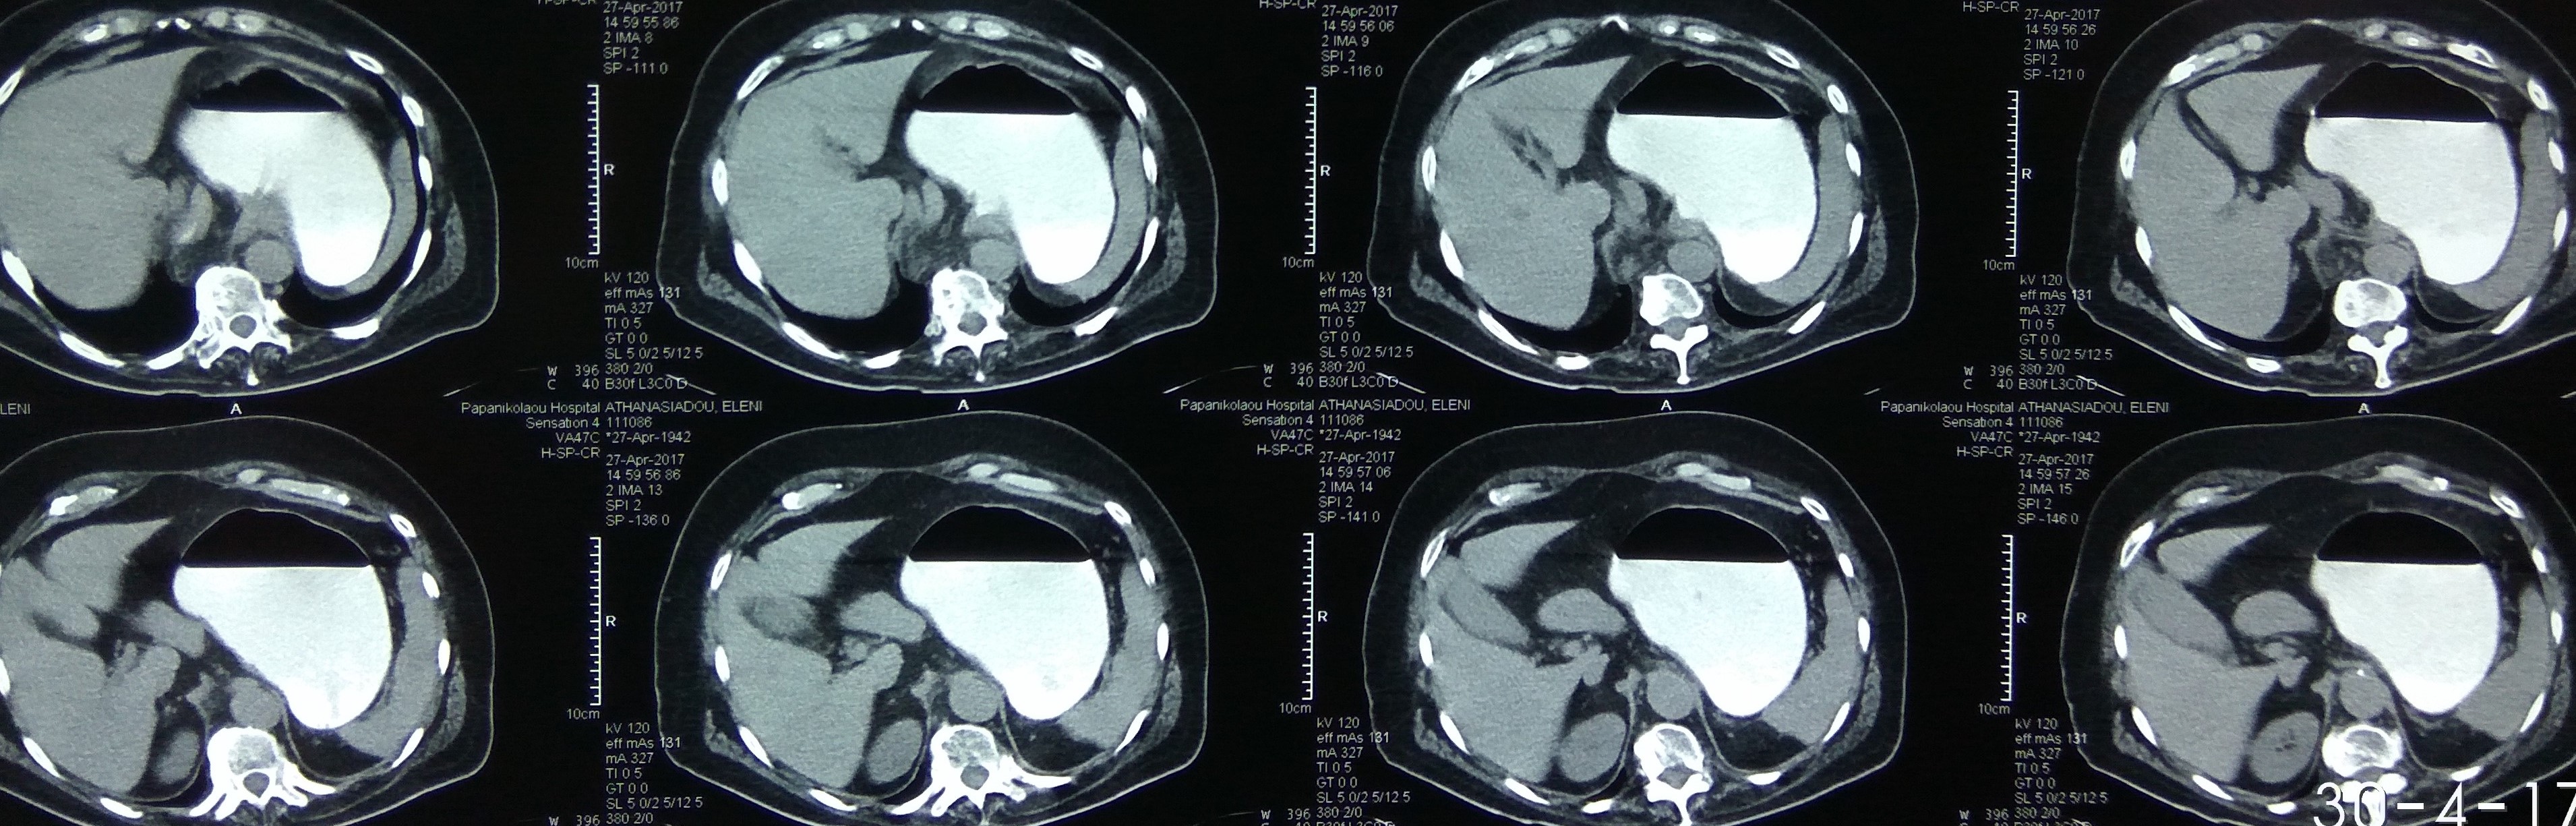

Different views of a double contrast-enhanced CT scan showing a left diaphragmatic hernia with an acute dilated stomach (Courtesy Dr. V. Penopoulos)